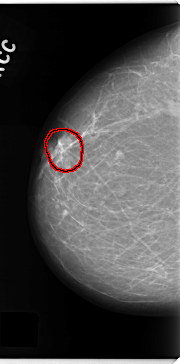

C_0155_1.RIGHT_CC

RIGHT_CC LINES 4720 PIXELS_PER_LINE 2328 BITS_PER_PIXEL 12 RESOLUTION 50 OVERLAY

FILE: C_0155_1.RIGHT_CC.OVERLAY

TOTAL_ABNORMALITIES 1

ABNORMALITY 1

LESION_TYPE MASS SHAPE OVAL MARGINS SPICULATED

ASSESSMENT 5

SUBTLETY 5

PATHOLOGY MALIGNANT

TOTAL_OUTLINES 1

BOUNDARY